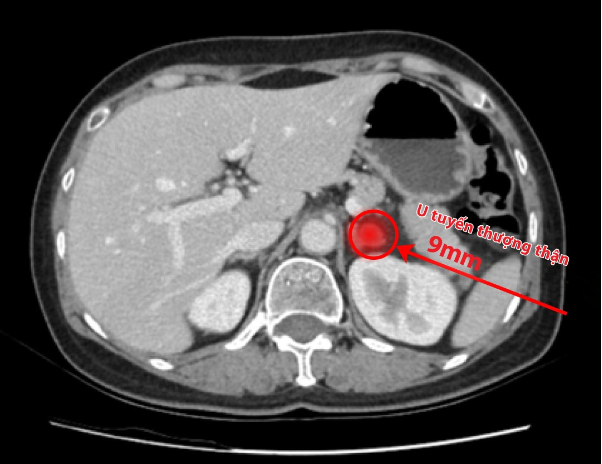

Để kiểm tra nghi ngờ trên, liên chuyên khoa Ngoại - Thận Nội tiết đã tiến hành hội chẩn, cho chỉ định chụp CT ổ bụng và các xét nghiệm đánh giá hoocmon tuyến thượng thận. Kết quả gây bất ngờ khi thực sự đã phát hiện ra một khối u kích thước siêu nhỏ chỉ 9mm ở tuyến thượng thận.

Khối u siêu nhỏ, nằm sâu trong phúc mạc, rất khó phát hiện